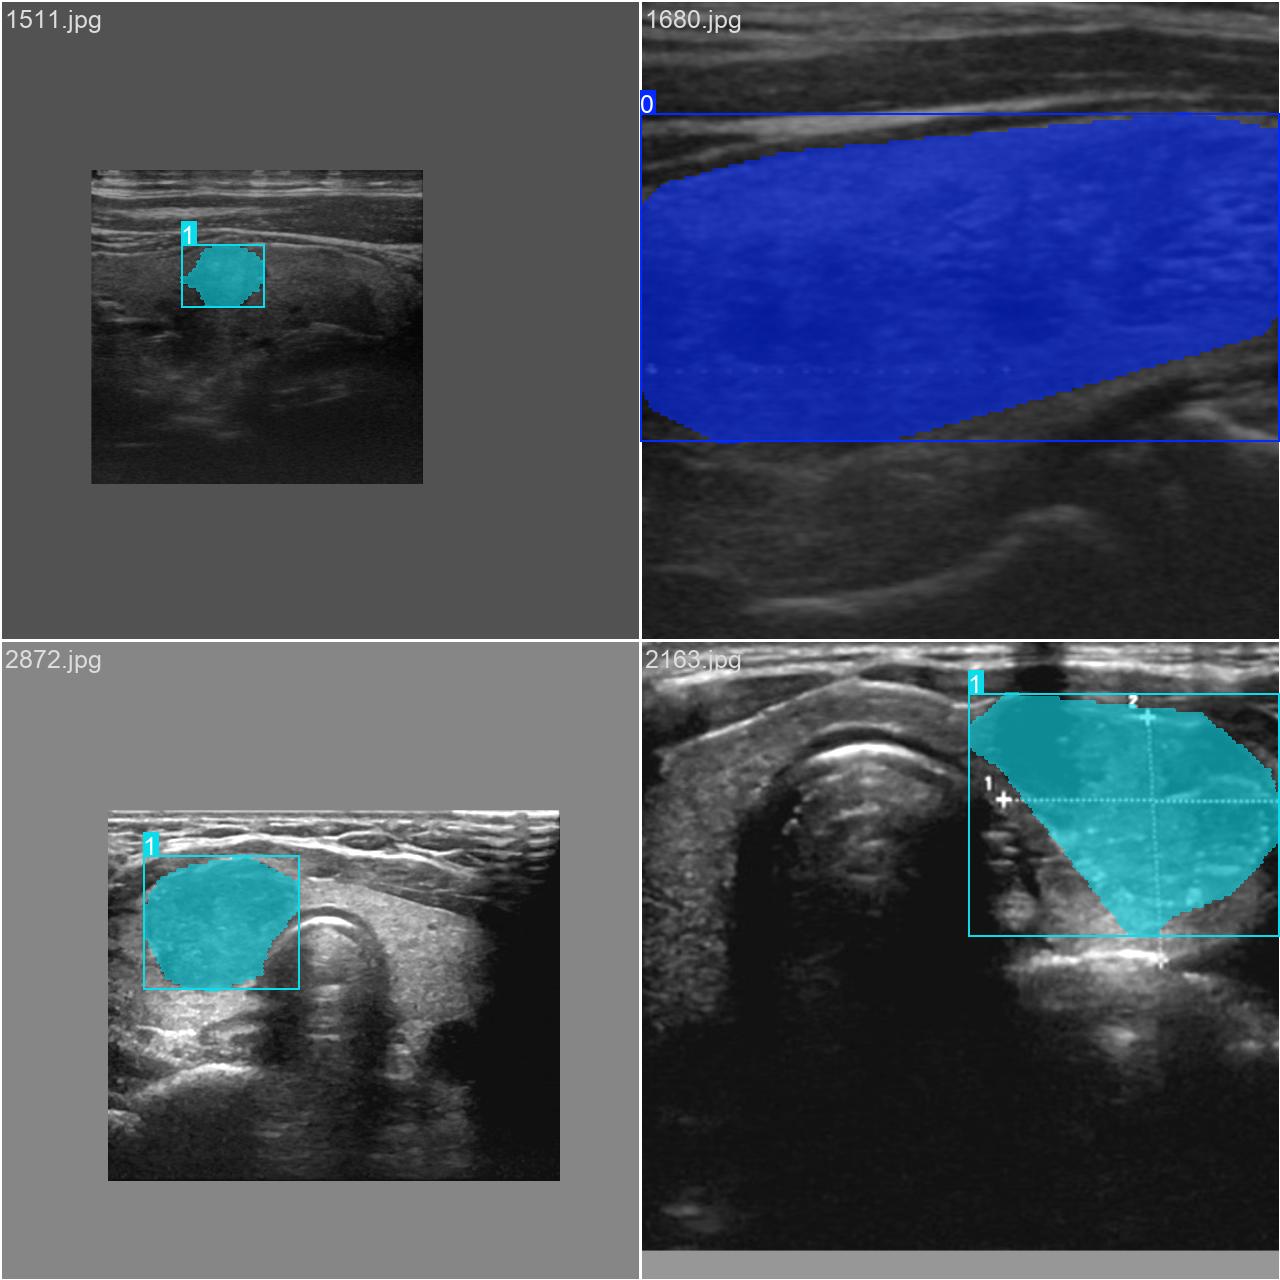

通过网络上搜集关于超声图像的甲状腺结节图片,并使用Labelme标注工具对每张图片中的分割结果及类别进行标注。一共包含3493张图片,其中训练集包含2879张图片,验证集包含614张图片,部分图像及标注如下图所示。